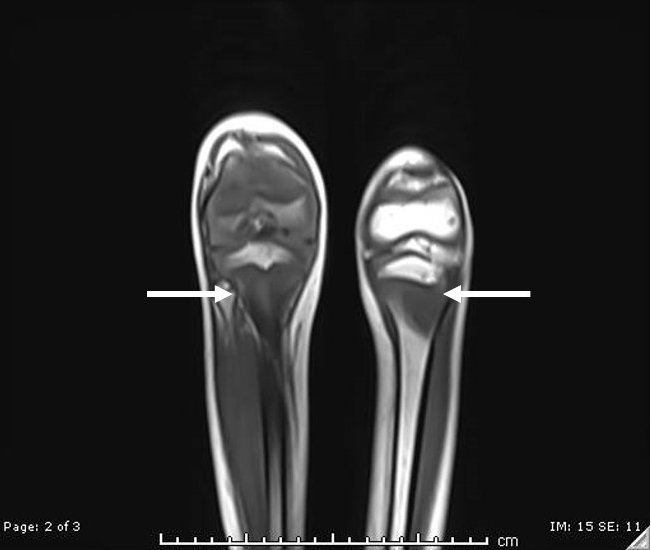

Scurvy. MRI T1-weight sequence. JETem 2021

A Boy with Rash and Joint Pain Diagnosed with Scurvy: A Case Report